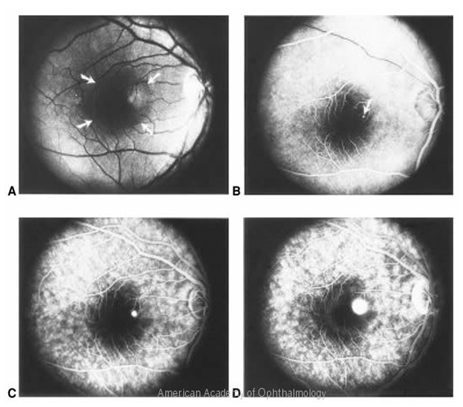

Is mainly divided into 1) blocked fluorescence and 2) vascular filling defect. Blocked fluorescence: Blocked fluorescence when stimulation or visualization fluorescein blocked by Blood. (Figure 12) (Figure 13) Pigment (Figure 14) Fibrosis vascular filling defect: (Figure 15) Vascular filling defect: Occurs when the retinal or choroidal vessels do not fill properly as in non-perfusion of artery vein. Capillary hyper fluorescence is mainly divided into 1) Autofluorescence 2) Transmission defect (window defect) 3) Leaking 4) Pooling and 5) Staining. Auto fluorescence: (Figure 16) compounds absorb blue light and emit yellow-green light in a similar fashion to fluorescein. It is imaged much more effectively by scanning laser ophthalmoscopy but can also be detected on standard fundus photography in exposed optic nerve head drusen and sometimes with Lipofuscin in retinal drusen and other abnormalities such as astrocytic hamartoma and angioid streaks. Transmission defect (window defect): (Figure 17) A window defect refers to the choroidal fluorescence produced by a relative decrease or absence of pigment in the RPE or an absence of RPE. The hyper fluorescence occurs early and reaches its greatest intensity with the peak of choroidal filling leaking: (Figure 18) Leakage of fluorescein dye is defined as hyper fluorescence of fluorescein in the extra vascular space. Typically the area of fluorescence increases in both size and intensity as the study progresses.

Figure 12 Patterns of hyper fluorescence or the hypo fluorescence

Figure 13A Stimulation of fluorescein blocked by Blood

Figure 13B Visualization fluorescein blocked by Blood.